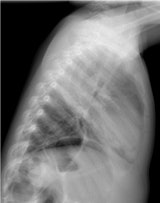

An article published online 6 July in Insights into Imaging reviews the radiological findings of various pediatric nontraumatic thoracic emergencies, and discusses how clinical presentation influences the choice of radiology exam, with an emphasis of keeping radiation dose as low as possible. X-ray exams remain the primary type of procedure ordered, followed by ultrasound exams and, only when necessary, CT and MRI scans.

Chest x-rays and ultrasound exams are most commonly performed to diagnose and monitor treatment of newborns and young infants. Respiratory infections, both bacterial and viral, are the most common. Congenital abnormalities of the airways can cause acute respiratory problems during pulmonary infections. While x-rays are initially recommended, multidetector CT scans with multiplanar reconstructions and volume-rendering are superior in depicting the anatomy.

Viral infections are more frequent than bacterial infections in infants and may cause pneumonia. Bacterial infections are more commonly diagnosed in children age 5 and older. Chest x-ray exams are the exam of choice, although approximately 30% of children with viral infections have normal chest radiographs.

Pleural empyema is increasingly being seen, both as a result of improved diagnosis and the reduced number of patients treated with antibiotics, according to de Lange. Chest radiographs and ultrasound exams should be the first exams ordered.

A CT scan should be ordered only when ultrasound and chest x-ray exams do not distinguish a loculated empyema from an intraparenchymal abscess or a cavitary necrosis/necrotizing pneumonia. Contrast-enhanced CT exams may be required to identify the position of drains, loculations, and parenchymal complications in patients who do not respond to treatment. Exposure to the CT radiation dose may also be warranted when imaging suppurative lung parenchymal complications because of CT's sensitivity and ability to detect and establish the extent of the complication.